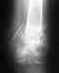

02/01/2012 года в 12.45 поппал в аварию. Доставлег в ЦГБ в 13 часов. Травму обнаружили только в 17 часов, после того, как начали опухать ноги. Переломы закрытые. В настоящее время лечу инфицированные раны, которые получились в связи с с тем, что не правильно наложили гипс- перетянули. В данный момент модрали кожу с ног и делают перевязки. Это продолжается уже с 10.01.2012г. Сегодя,16.01.2012г мне делают повторные снимки ног без гипса. Готовят к операции. ЭЖду От Вас дальнейших рекомендаций. С ув,Морозов.